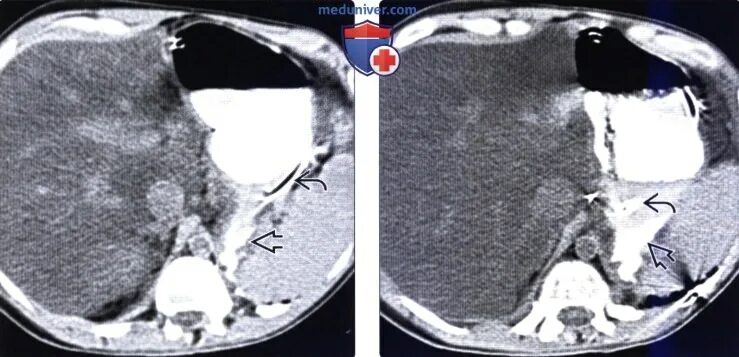

Язва желудка кт